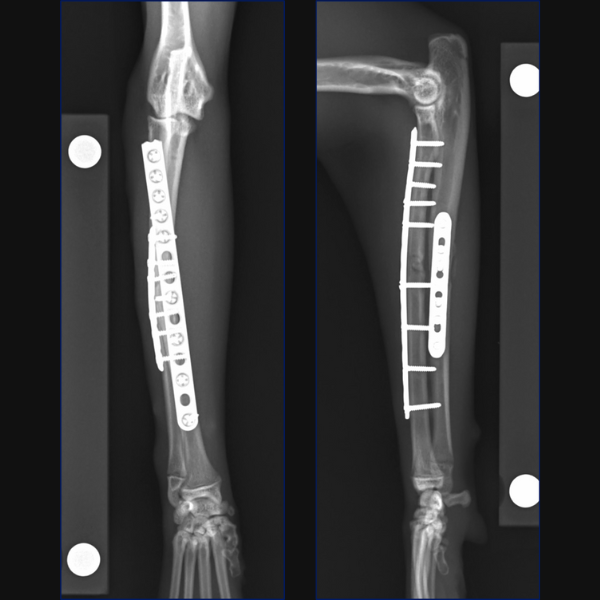

For Bundle we performed open reduction and internal fixation using a 14-hole 1.5/2.0 Veterinary Cuttable Plate (VCP) on the radius and a 6-hole 1.5mm Locking Compression Plate (LCP) on the ulna. This was all performed through single craniolateral approach. I think we have addressed one reason why we chose dual bone fixation in this case, due to the lower complication rate that could be anticipated with that. Another reason is that in people at least, insufficient stabilization has been associated with an increased risk of synostosis formation so rigid, dual-bone fixation was desired here to limit that. But why choose a lateral plate on the ulna rather than an IM pin?

You could debate the choice of a single approach for fixation here based on some literature in the human field. I have generally preferred a single approach with the suture line not lying directly over either of my implants but that is simple personal preference. While it is based on a very specific posterior approach to the radius and ulna called the Boyd approach, and may not be transferrable to our feline patients, there is some evidence in humans with radius-ulna fractures that placement of dual bone fixation through a single approach is associated with a higher risk of synostosis formation than placement of implants through two separate approaches. Postulated reasons include extensive soft-tissue exposure, increased risk of development of radioulnar hematoma or interosseous damage and potential malpositioning of one of the implants due to suboptimal exposure of both bones. Further research is required to determine whether single or dual approaches may be associated with different complication rates in cats, but certainly, you could argue that the radial plate is positioned slightly too laterally at the proximal extent here and that a single approach may have contributed to that.

In terms of critiquing my postoperative radiographs here from Figure 3, in addition to the radial plate being slightly too lateral at the proximal extent, the first screw distal to the fracture is close to caudodistal extent of the short oblique fracture line. This may have rendered this screw monocortical and additionally, may have caused some fragmentation of the fracture line at this point, so not ideal, but we do have an additional three bicortical screws distally on the radius in addition to three screws in the ulna so I did not consider that this warranted any immediate revision surgery.